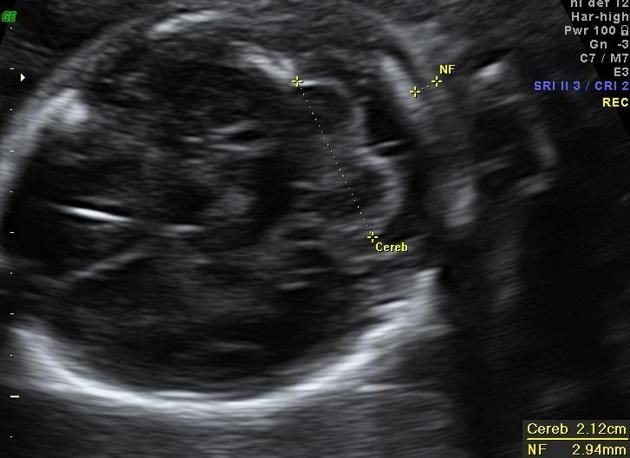

Второй скрининг, шейная складка

По мозгу вот что измеряют. Но , если вам сказали, что всё нормально, то не надо до каждой цифры докапываться)) выдохните и расслабьтесь) Изображение

Мне кажется это отдел мозга какой-то измеряли. В этом срезе по идее шеи не видно. Я не спец, конечно